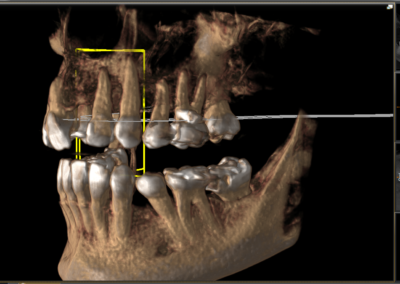

We start with a comprehensive full mouth examination, digital X-rays, a dental 3D(CBCT) scan and Trios5 Scan. The scanned images provide high-resolution images in a three dimensional plane. We use these images and scans for precise treatment planning.

CBCT 3D Scan

Using the 3D images in special planning software, the Dentist maps out the exact position and angle of insertion of each implant. They take care to place implants where they will be stable and in the best position to support the replacement teeth. They will also plan out any bone grafting (if needed) to ensure the implants have strong bone support.